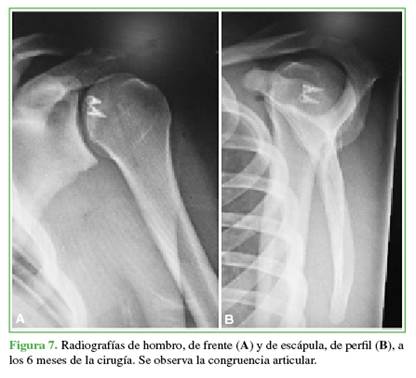

El tiempo quirúrgico osciló entre 80 y 150 min (promedio 100). No hubo reluxaciones, infecciones ni signos de inestabilidad en ninguno de los 3 pacientes (Figura 7).